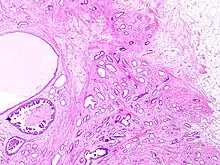

Tubular carcinoma is a subtype of invasive ductal carcinoma of the breast.[2][3] More rarely, tubular carcinomas may arise in the pancreas[4] or kidney.[5] Most tubular carcinomas begin in the milk duct of the breast and spread to healthy tissue around it.[6][7]

Although tubular carcinoma has been considered a special-type tumor,[lower-alpha 1] recent trend has been to classify it as a low-grade, invasive NOS carcinoma because there is a continuous spectrum from pure tubular carcinomas to mixed NOS[lower-alpha 2] carcinomas with tubular features, depending on the percentage of the lesion that displays tubular features.[10]: 647

Tubular carcinomas are generally around 1 cm. or smaller, and are made up of tubules. They are usually low-grade.[2] Elastosis has been noted as common but is not present in all cases.[11]

A highly differentiated invasive carcinoma that forms well-defined tubules (containing epithelium, but no myoepithelium) and that have abundant desmoplastic fibrous stromal reaction between the tubules.